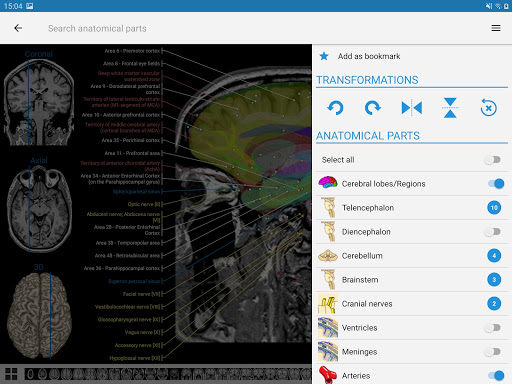

* اعثر على الأجزاء التشريحية الخاصة بك بسهولة أكبر بفضل ميزة البحث الجديدة والأكثر سهولة وقوة

* تحسين رؤية تعريفات الأجزاء التشريحية

* تصفح بين الأجزاء التشريحية باستخدام روابط الوصف